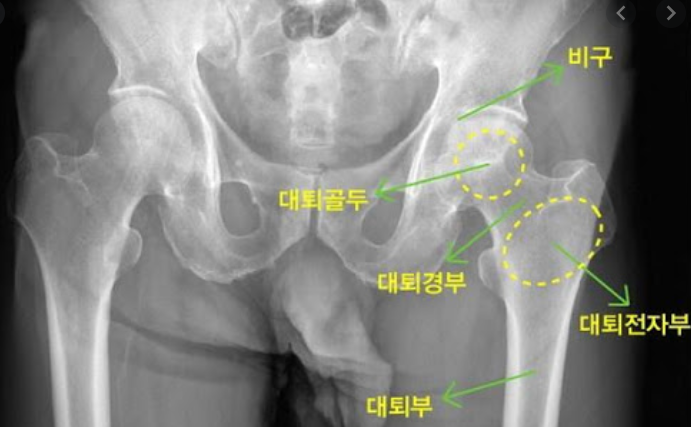

고관절은 골반과 대퇴골을 이어주는 관절입니다. 그래서 엉덩이관절, 엉덩관절 등 여러명칭으로 불리고 있습니다. 고관절이 불편하거나 통증이 있다면 하체를 움직이기에 불편함이 커집니다.